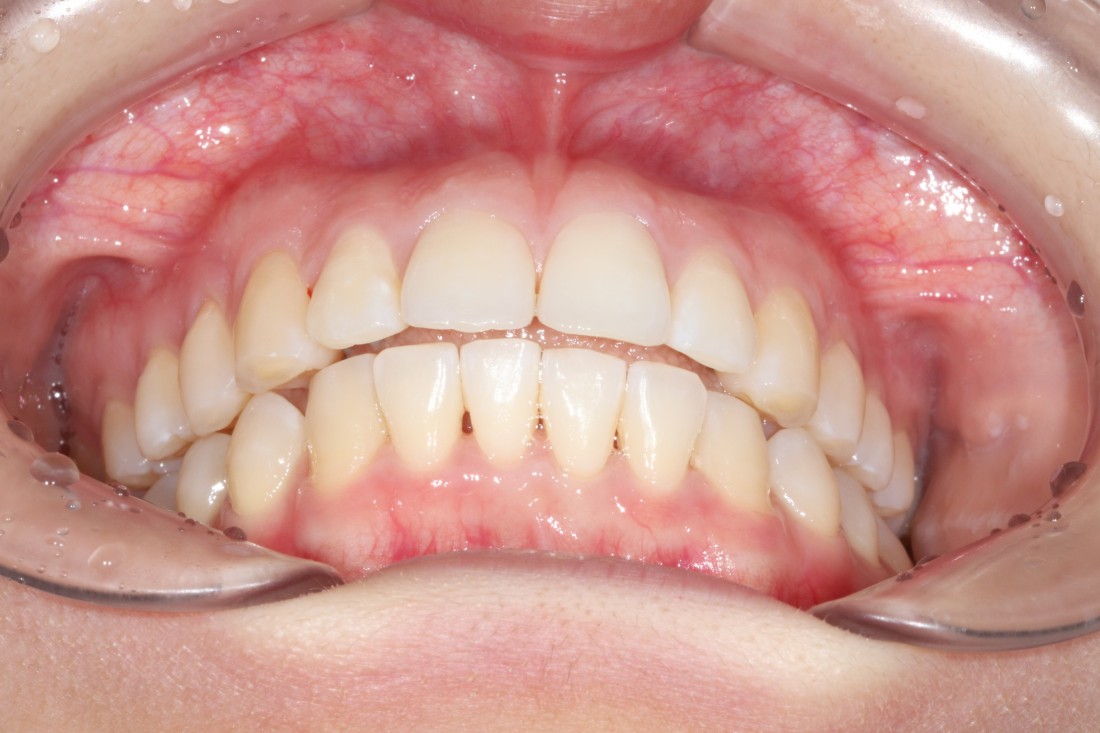

광주 교정치과를 추천하는 이유는

수 백가지가 넘는 교정 케이스를

보유하고 공개하고 있는 교정치과이기 때문에

실력을 믿을 수 있기 때문입니다.